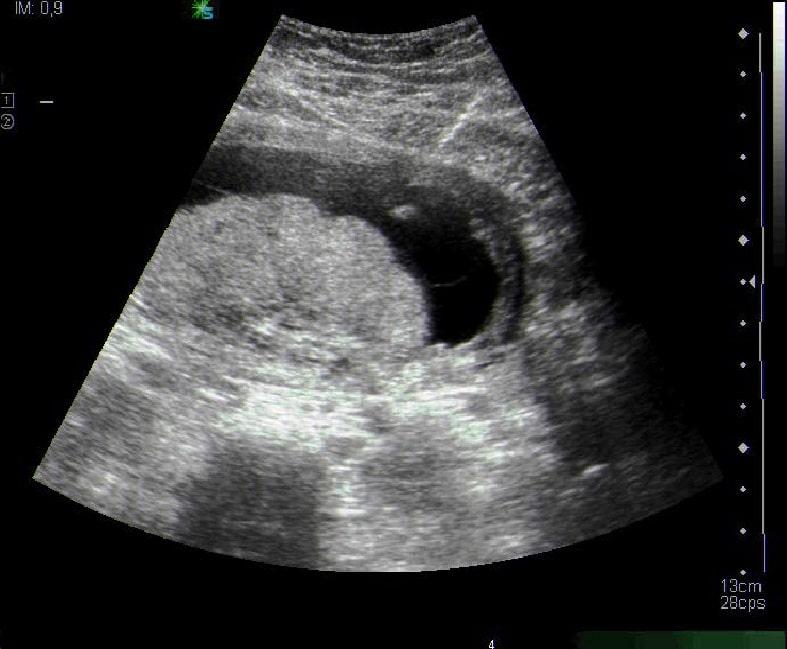

Un dels objectius primordials que les doctores han plantejat és l’actualització d’un eix vertebrador del diagnòstic prenatal: la tècnica ecogràfica, a través de la qual es pot observar amb detall la morfologia facial del fetus i definir si pateix malformacions dismorfològiques.